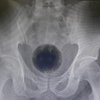

Um homem foi parar na emergência após ter fortes dores abdominais. Foi constatado, por meio de raio-x, que o corpo estranho se tratava de um tubo de desodorante. O objeto estava retido no ânus há três semanas. Ele teve que passar por cirurgia e o procedimento durou 2 horas.  O caso aconteceu em West Bengal, na Índia.

O paciente de 27 anos, com o nome não revelado, teve dano no esôfago e intestino. Ele ficou hospitalizado e não foi capaz de evacuar durante este período. De acordo com a equipe médica, em entrevista ao canal de notícias India’s News18, ele corria risco de vida se não retirasse o objeto do corpo.

Mesmo com a cirurgia, o paciente não se recuperou totalmente. O homem deve passar por outros procedimentos para reparar a situação.